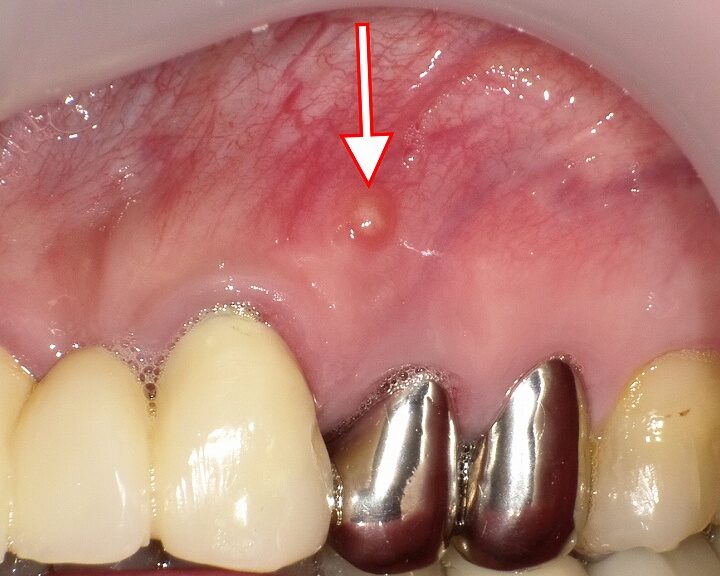

歯茎のフィステルは、さまざまな要因によって引き起こされます。そのメカニズムを理解することは、効果的な治療法を見つけるために重要です。主な原因としては、感染症や虫歯、歯周病が挙げられます。これらの状態が進行すると、炎症と膿が形成され、その結果としてフィステルが発生します。

虫歯は初期段階であれば治療可能ですが、進行すると神経まで達しやすくなります。この段階で適切な処置を受けないと、「根管」部分に感染がおよび、大きな問題につながります。その結果としてフィステルが形成されることがあります。

また、牙周ポケット内で繁殖したバイ菌は持続的な炎症を引き起こし、その後に骨吸収や軟組織損傷を招くことになります。こうした過程もフィステルの原因となり得るため、自覚症状なく進行している場合には注意深いケアと定期的な検診が求められます。